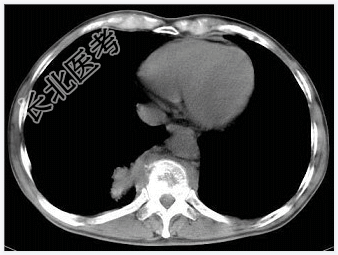

- [材料题] 男,32岁,低热、腰背痛,活动受限。

- 简答题1、结合CT检查,最可能的诊断是?

- 简答题3、椎体结核的诊断方法有哪些?